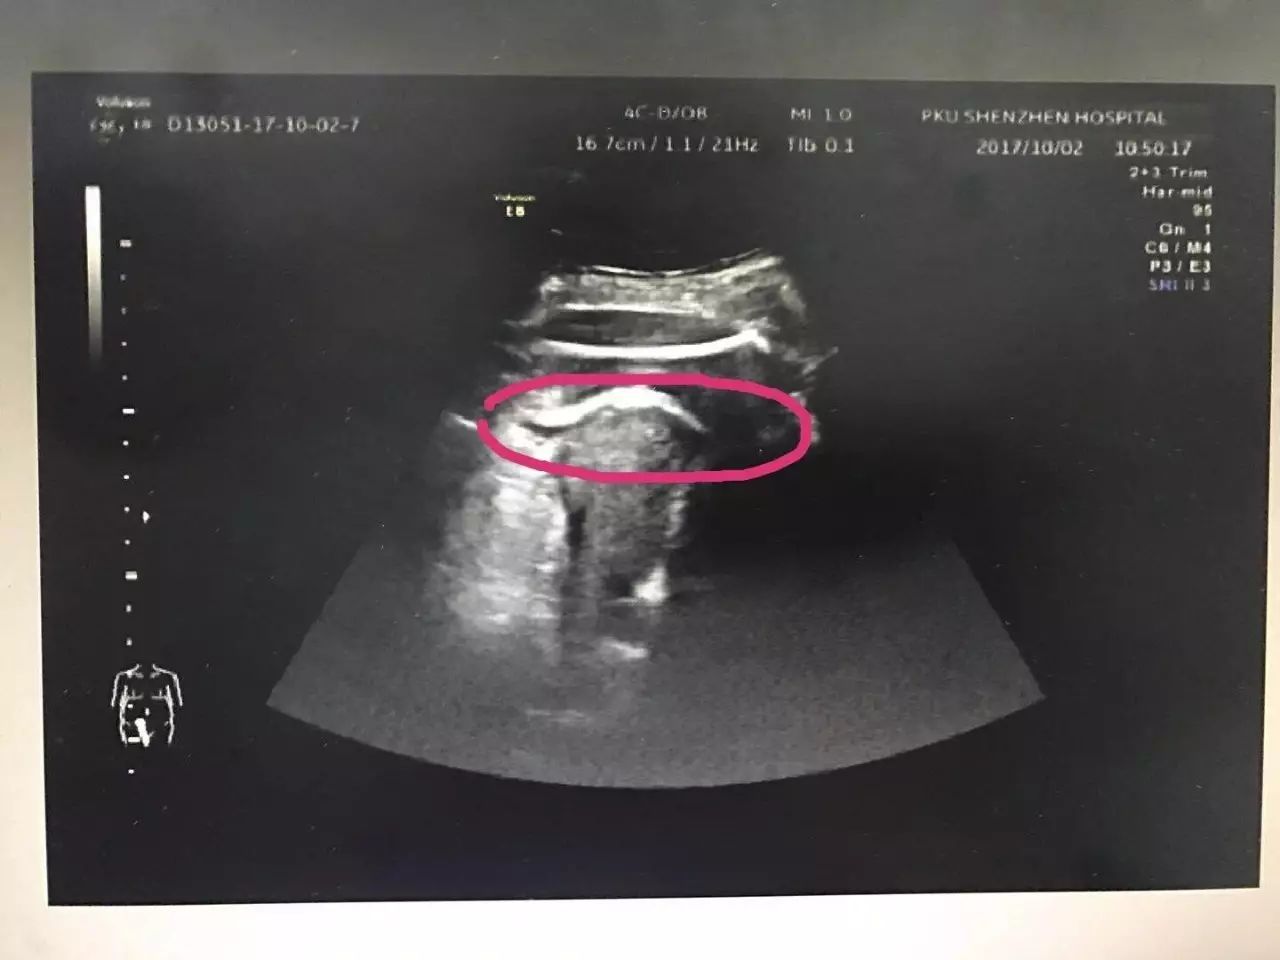

怀孕35周的头胎准妈妈张女士突然上腹痛还以为是胃疼,没想到被送往医院急诊时已经腹痛难忍,多项生命体征都在恶化。B超发现,胎儿的一条腿踹穿子宫,进入腹腔,大腿根卡在子宫壁上。

原来张女士在去年做过子宫肌瘤剔除术,术后半年就怀孕了,医生作出的诊断是高度怀疑为疤痕子宫破裂。幸好医生当机立断10分钟内剖出胎儿,母子平安。